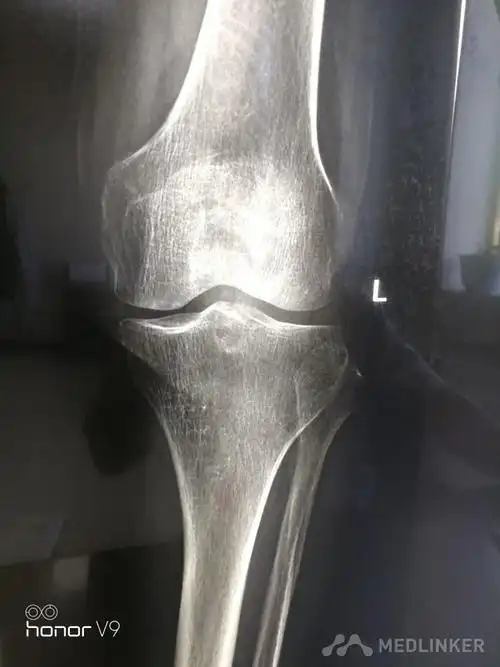

左侧髌骨骨折